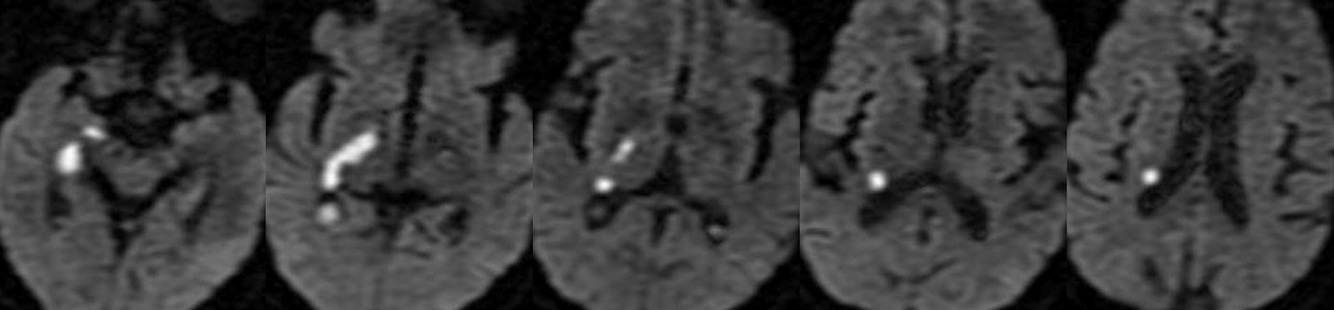

Image on left is SWI

Image on right is DWI